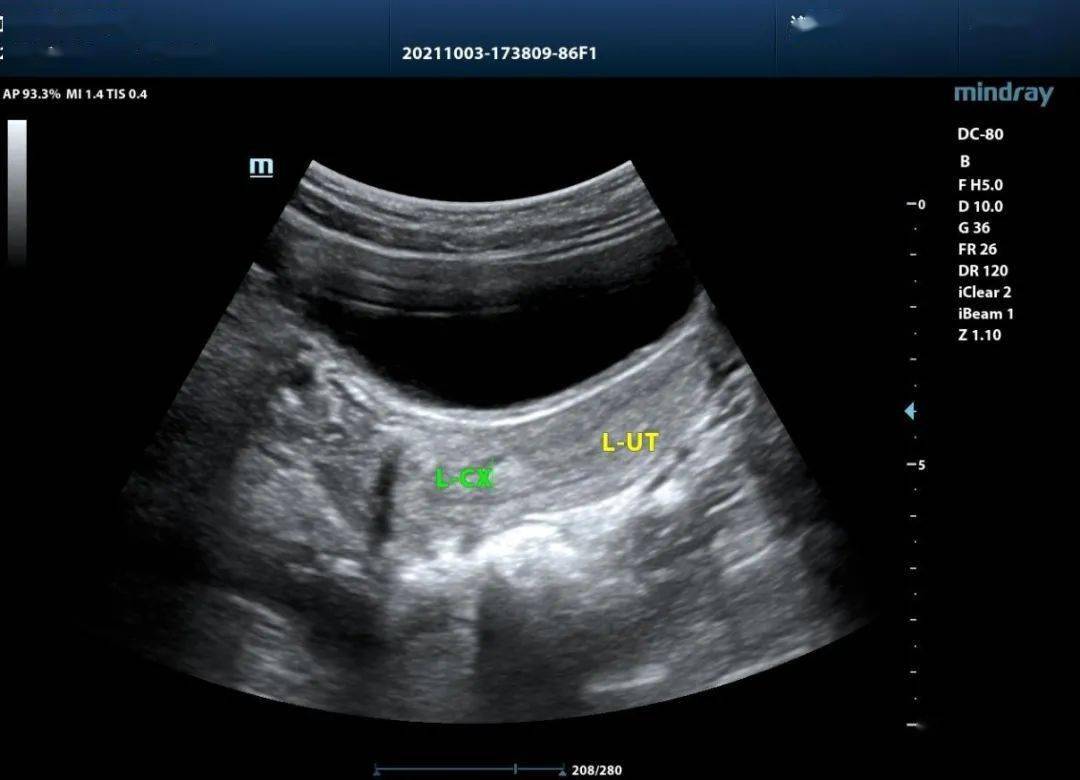

所有病患没有阴道镜检查和子宫切除、子宫颈上皮内瘤 样病变既往史。 1.2 方法 在检查操作前24h 受检者应禁止性生活,不可进行阴道冲洗、用药、检查等 检查时取截石位,运用阴道窥器将宫颈做充分暴露,将宫颈分泌物擦拭干净, 对宫颈颜色、形态、血管等情况进行检查,在宫颈运用5%酸醋做涂抹,而后对 转化区、血管、上皮的变化做观察。对宫颈涂抹1%碘溶液进行碘试验,当柱状、 未成熟化生、角化、非典型等上皮出现碘不着色的情况为阴性表现,则需要进行 部位的活检,如果阴道镜检查没有发现异常,则进行3、6、9、12 点的活检。 1.3 评估观察 阴道镜的正常检查情况为图像为原始的柱状上皮、鳞状上皮和正常转化区情 况,异常情况则图像有镶嵌、白斑、點状血管、畸形血管、醋酸白色上皮或者碘阴 性表现。而后记录阴道镜检查和病理检查的病变与正常情况的人数,两者做对比 1.4 统计学分析 .将采集到的数据通过spss17.0 统计学软件做分析处理,计数资料运用卡方 来检验,以P<0.05 作为组间差异具有统计学意义的标准。 结果通过表1 可知,阴道镜下结果与病理活检的结果符合率较高,两组差异不明显;同时检出率年龄段主要集中在31-50 岁年龄段,其中41-50 发年龄段,子宫颈癌、子宫颈上皮内瘤变的比例均为最高。

表1:受检者者阴道镜检查结果与病理检查的比较 表2:阴道镜下活检病理结果与年龄的关系 讨论阴道镜可以对子宫颈表面进行微小病变的观察,替代肉眼无法识别的病变, 主要是对子宫颈结构、形态、颜色和碘反应做观察,例如异常血管、醋酸白色上 皮等。一般情况上显示为白色上皮情况较多,最具价值的图像以镶嵌异形血管、 点状血管等。而随着异常图像显示的情况和级别增高,病理结果的诊断中相关恶 性疾病的检出率也逐步提升。部分情况下炎症也会有阴道镜检验的异常图像出现 这种情况与对阴道镜显示图像上白色上皮的掌握程度欠缺,特别是非典型性的 增生和未成熟的上皮醋酸白色反应在一定程度上,形态上较难区分【2-3】。 在临床诊断上,不能仅仅依靠阴道镜的图像显示来对子宫颈病变做诊断, 需要根据病史、临床症状表现和病理学检验结果为准。阴道镜的检查结果准确性 与医生的视觉技术、经验等综合能力有关,对阴道镜的图像理解能力带有一定的 主观判断性,因此,在准确性上具有一定的失准可能性。因此,虽然阴道镜对子 宫颈病变的诊断具有一定重要作用,但是一定要结合病理检查结果进行综合评 估,这样才能保证诊断的准确性。 组织病理学检验是诊断子宫颈病变的金标准,阴道镜检查的结果主要依靠 病理结果来确定。